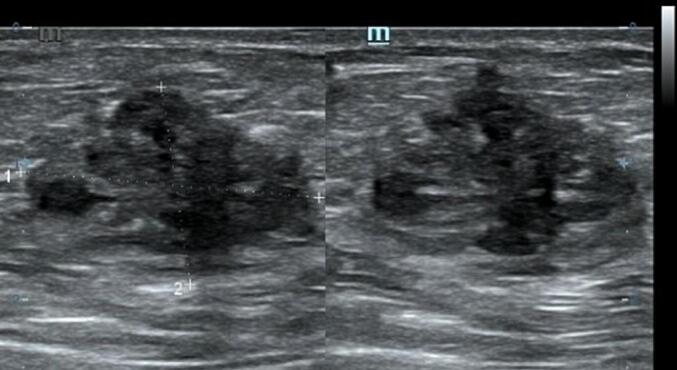

Cutaneous examination reveals a painful, well-defined, nodular tender mass, 2 × 2 cm in size in the umbilical region of the abdomen. Upon the abdominal ultrasonography (US) examination, we found an inhomogen hypoechoic lesion, hypovascular, 2,12 × 1,46 × 1,96 cm in size with posterior shadowing in the umbilical region of the abdomen suggestive of umbilical endometriosis (Fig. 6).

Fig. 6.

Ultrasonography examination of the second patient showed an inhomogen hypoechoic lesion, hypovascular, 2,12 × 1,46 × 1,96 cm in size with posterior shadowing in the umbilical region of the abdomen.

Abdominal ultrasonography (US) is the first line and cost efficient diagnostic tool that was used in both of these patients. On ultrasonography, AWE lesion will appear as a heterogenous isoechoic or hypoechoic area surrounded by peripheral vascularization [3,15]. While US remains the best screening tool, CT scan provides better results when endometriosis is located at the muscle or subcutaneous layer and MRI is superior for small lesions [3,15].